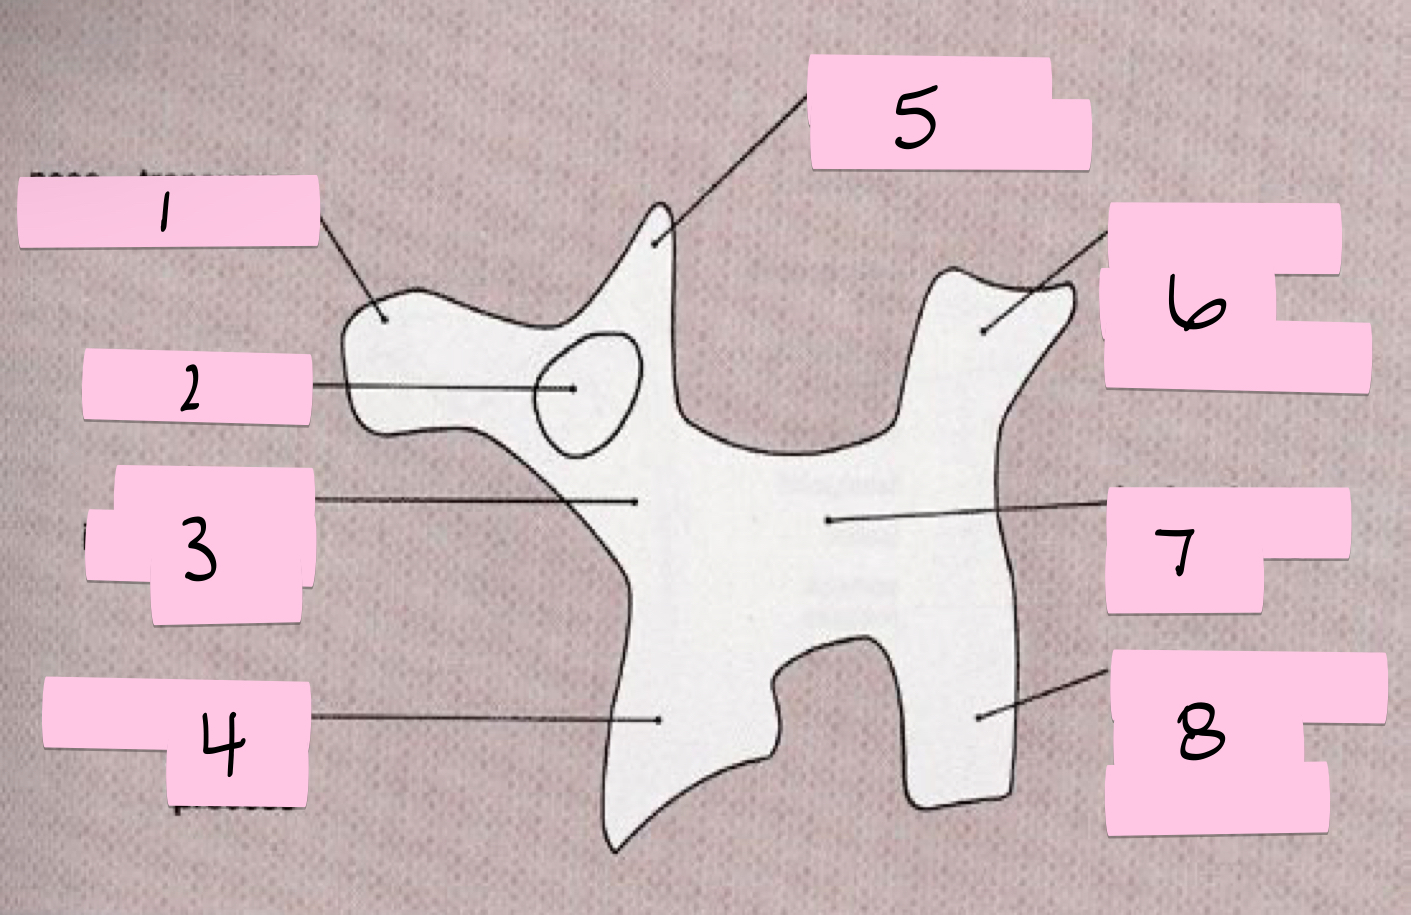

What is 1 pointing to?

Nose- Transverse process

What is 2 pointing to?

Eye- Pedicle

What is 3 pointing to?

Neck- Pars interacticularis (isthmus)

What is 4 pointing to?

Foreleg- Inferior articular process

What is 5 pointing to?

Ear- Superior articular process

What is 6 pointing to?

Tail- Superior articular process of opposite side

What is 7 pointing to?

Body- Lamina and spinous process

What is 8 pointing to?

Hindleg- Inferior articular process of opposite side